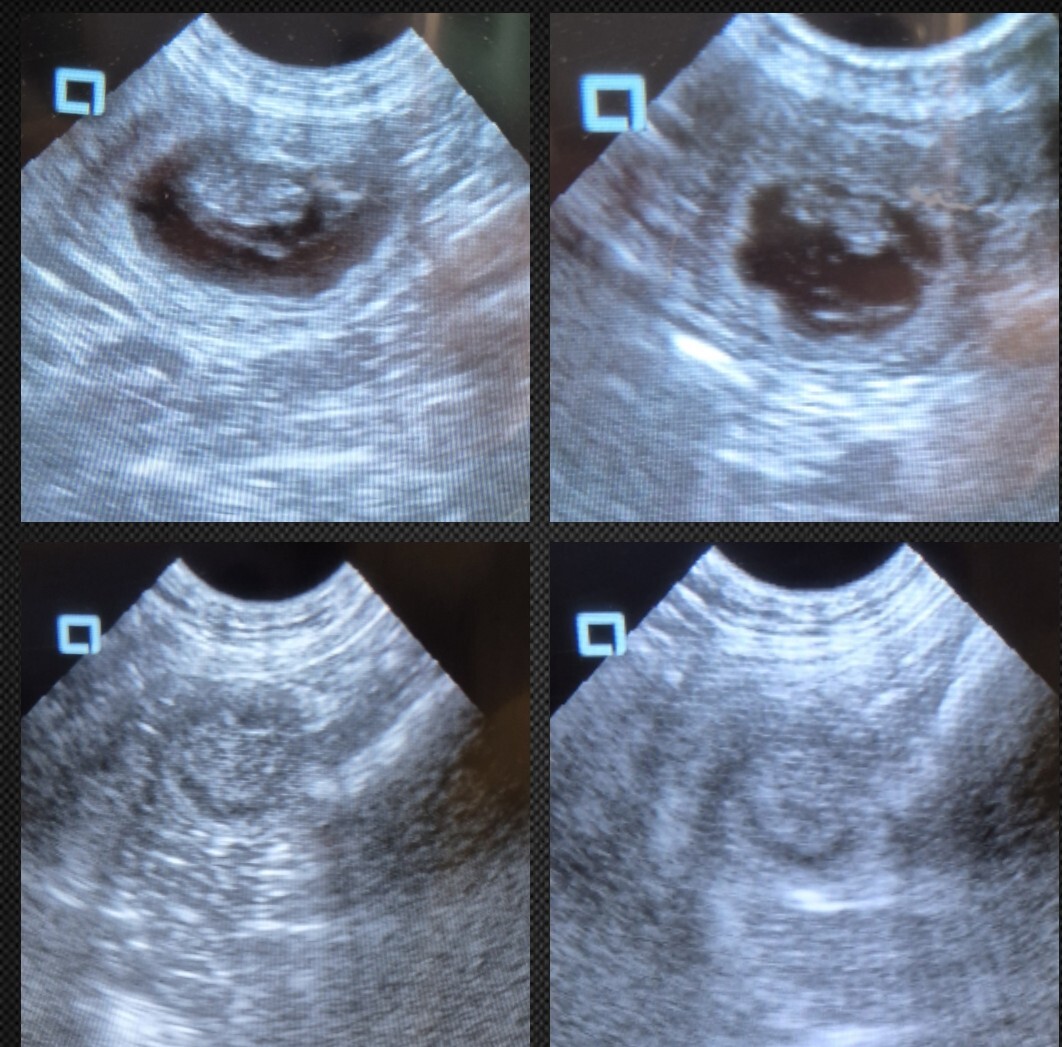

We recently received a powerful illustration of foetal resorption through a series of ultrasound images shared by *Joanne Smith, an experienced pregnancy scanner. Joanne used her trusted ScanPad ultrasound machine—still going strong more than six years after it was recommended to her during her level one training. The ScanPad, available at PUM, remains one of the most reliable machines on the market, and Joanne’s continued use of it is testament to both its durability and performance.

In this case, Joanne was monitoring a dog carrying a singleton pregnancy—a single pup—which carries inherently increased risks. Unfortunately, the foetus was found to be non-viable. However, because Joanne had taken images earlier in the pregnancy, she now has rare and valuable “before, during and after” comparison images that clearly show the progression of the resorption process:

She continues to monitor the dog closely, and although the story is still unfolding, the quality of her scanning and documentation offers a vital learning opportunity for others.